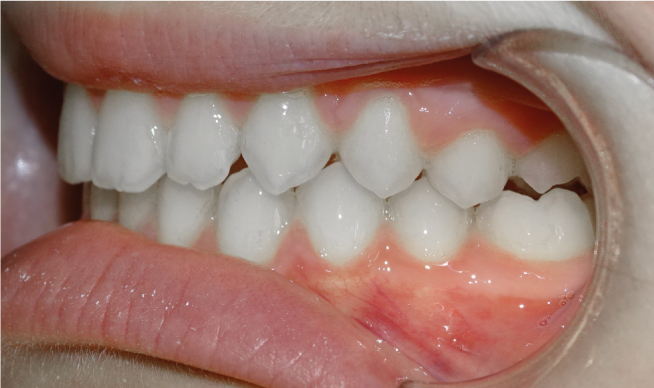

La classe II, c’est quand la mâchoire du bas est en arrière de la mâchoire du haut, donnant l’effet de “dents en avant” pour la mâchoire du haut. Si c’est normal à la naissance, Ceci paraitrait normal à la naissance et tend à se corriger avec l’allaitement maternel et la recherche de contacts entre les incisives du haut et du bas. Au plus on intervient tôt, au plus la mâchoire du bas va rattraper la mâchoire du haut ; au plus on attend, au plus on reculera le haut sur le bas avec des conséquences sur l’esthétique du profil et la capacité ventilatoire nasale.

Dans le cas d’une Classe II :

• La lèvre du bas s’interpose entre les 2 mâchoires

• Le sourire est étroit, tendance à l’écrasement du bas du visage